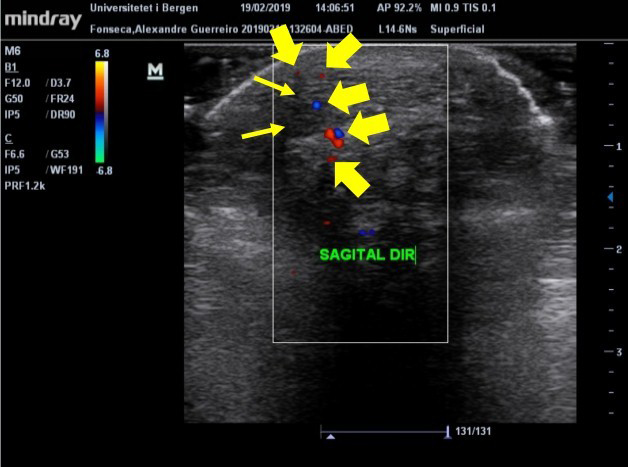

O tendão do calcâneo (TC) é o mais forte tendão do corpo humano, com grande capacidade de suportar carga. O TC é vulnerável a lesões por esforço repetitivo por receber muita carga, responsável por 18% de todas as lesões no esporte. O ultrassom (US) diagnóstico é uma técnica barata, dinâmica e rápida para avaliação de tecidos tendíneos, que pode ser associada a testes clínicos para diagnóstico de tendinopatias. Considerando que a simetria do organismo está relacionada com bom estado geral de saúde, objetivou-se neste trabalho avaliar a morfologia e aspectos clínicos do TC de indivíduos com e sem tendinopatia do TC. Participaram do estudo 28 indivíduos: 15 no grupo controle (GC) e 13 no grupo tendinopatia (GT). Os participantes passaram por avaliações específicas do TC: Exame de US, testes à palpação e clínicos. Os sujeitos do GC apresentam média de 0,407cm e 0,389cm da espessura do TC (TC direito e TC esquerdo), e não foram demonstradas anormalidades que indicassem inflamação nas imagens de US e nos testes clínicos. Nos indivíduos do GT, os valores da espessura do TC foram maiores, atingindo até 0,563cm, além de apresentarem alterações nas imagens de US para inflamação. A diferença da espessura do TC entre membros dos indivíduos do GC foi de 10%, enquanto no GT foi de 22%. Por meio dos resultados, sugere-se que diferenças da espessura do TC superiores a 20% indiquem a presença de tendinopatia, comprovadas pelos achados nas imagens de ultrassom e pelos resultados positivos dos testes à palpação e clínicos.Downloads